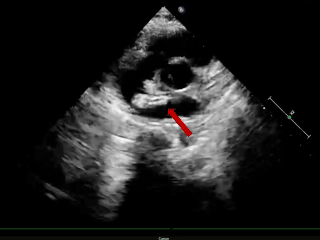

超声多切面确认

封堵器骑跨房间隔两侧

五腔心切面

剑下双房心切面